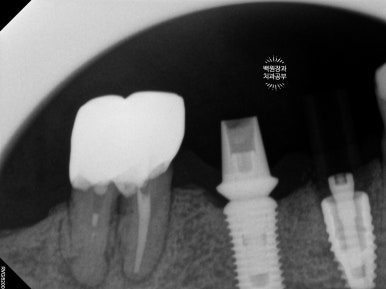

오른쪽 아래 작은어금니에 스트라우만 임플란트를 심고 골이식을 했습니다.

이를 뽑으면서 동시에 임플란트를 심는 발치 즉시 임플란트의 경우, 뼈이식이 필수적으로 동반될 수밖에 없습니다.

오른쪽 아래 작은어금니는 기존의 임플란트와 합치기로 하였어요.

오른쪽 아래 임플란트는 음식이 많이 낀다는 이유로 임플란트 크라운 재제작을 원하셔서, 머리부분만 제거하고 새로 2개짜리 임플란트 크라운으로 제작하기로 하였습니다.

임플란트 크라운을 묶어주면 보다 튼튼해진다는 장점과 음식이 덜 낀다는 두가지 장점을 함께 가져갈 수 있습니다.

스트라우만 임플란트를 사용하여 수술하였던 어금니 부위에 임플란트 머리가 제작되었습니다!

상당히 많은 임플란트를 가지고 계시지만, 다행히 그 사이에 예쁘게 쏙 심어내었답니다 :)

약간 생긴게 다른데, 임플란트도 회사마다 보통 약 3-4가지 라인업이 있기 때문입니다. 스트라우만 임플란트의 경우 크게 Standard, BLT, BLX 라인이 있으니 형태가 달라도 놀라지 마세요! 상황마다 용도가 다를 뿐입니다.